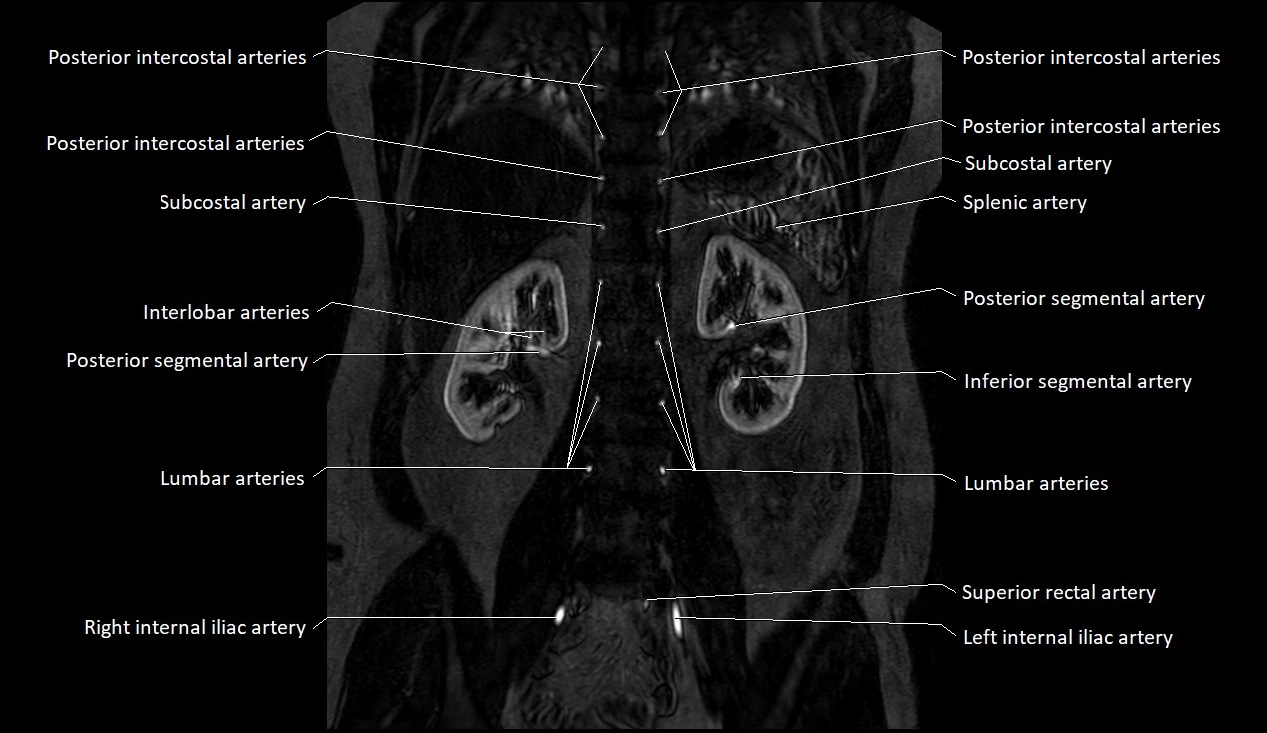

MRA (Magnetic Resonance Angiography):

• Contrast-enhanced MRA provides high-resolution imaging of the aorta and its branches

• Allows 3D reconstruction of visceral, parietal, and terminal branches

• Excellent for evaluating aneurysm size, dissection flap, stenosis, or preoperative planning

• Non-invasive alternative to conventional angiography

MRI images

image